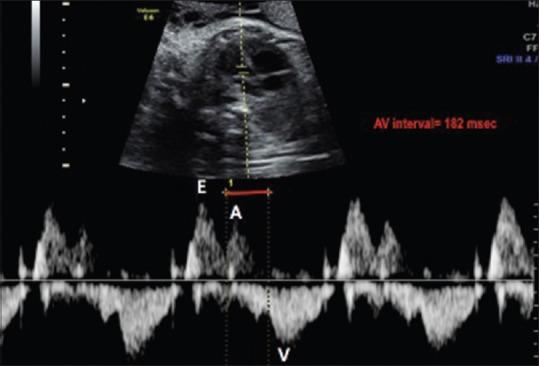

This article reviews important features for improving the diagnosis of fetal arrhythmias by ultrasound in prenatal cardiac screening and echocardiography. Transient fetal arrhythmias are more common than persistent fetal arrhythmias. However, persistent severe bradycardia and sustained tachycardia may cause fetal hydrops, preterm delivery, and higher perinatal morbidity and mortality. Hence, the diagnosis of these arrhythmias during the routine obstetric ultrasound, before the progression to hydrops, is crucial and represents a challenge that involves a team of specialists and subspecialists on fetal ultrasonography. The images in this review highlight normal cardiac rhythms as well as pathologic cases consistent with premature atrial and ventricular contractions, heart block, supraventricular tachycardia (VT), atrial flutter, and VT. In this review, the details of a variety of arrhythmias in fetuses were provided by M-mode and Doppler ultrasound/echocardiography with high-quality imaging, enhancing diagnostic accuracy. Moreover, an update on the intrauterine management and treatment of many arrhythmias is provided, focusing on improving outcomes to enable planned delivery and perinatal management.

本文综述了在产前心脏筛查和超声心动图检查中,通过超声改善胎儿心律失常诊断的重要特征。短暂性胎儿心律失常比持续性胎儿心律失常更为常见。然而,持续性严重心动过缓和持续性心动过速可能导致胎儿水肿、早产以及更高的围产期发病率和死亡率。因此,在常规产科超声检查期间,在进展为水肿之前诊断这些心律失常至关重要,并且是一项挑战,需要胎儿超声检查方面的一组专家和亚专科医生参与。本综述中的图像突出了正常心律以及与房性和室性早搏、心脏传导阻滞、室上性心动过速(VT)、心房扑动和VT一致的病理病例。在本综述中,通过M型和多普勒超声/超声心动图高质量成像提供了胎儿各种心律失常的详细信息,提高了诊断准确性。此外,还提供了许多心律失常的宫内管理和治疗的最新情况,重点是改善结局,以实现计划分娩和围产期管理。